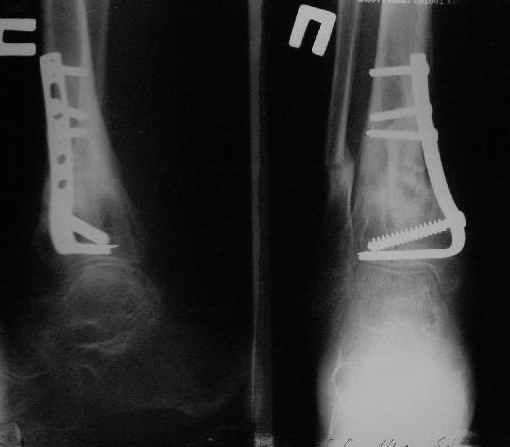

Операции: 1 Клиновидная резекция на вершине деформации м\берцовой кости.

2 Тугоподвижный ложный сустав н\3 б\берцовой кости. Рубцы выполняющие пространство между отломками, канал проксимального отломка иссечены.

Одномоментное устранение деформации, остеосинтез Г-образной пластиной.

Пластика по Хахутову.

Заживление проксимальной части раны вторичным натяжением без нагноения. Рана зажила. Спицы удалены через 1,5 недели после операции.

Особого смысла в них не было.

Учитывая фон (интеллект, etc) гипсовая повязка.

На данный момент ходит при помощи костыля (без присмотра -без костыля :), разрабатывает движения в г\стопном суставе.

Фиксация

|